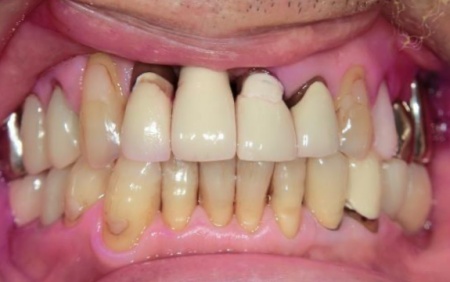

70代男性 右下奥歯を抜いてインプラント治療で噛み合わせを回復した症例

拝見したところ、右下奥歯(第2小臼歯)の周辺組織に炎症が広がり、歯茎が赤く腫れていました。

メリット:天然歯に近い見た目や噛み心地が期待できる

最後に完成した被せ物を装着し、見た目や噛み合わせに問題がないことを確認して、治療を終了しています。